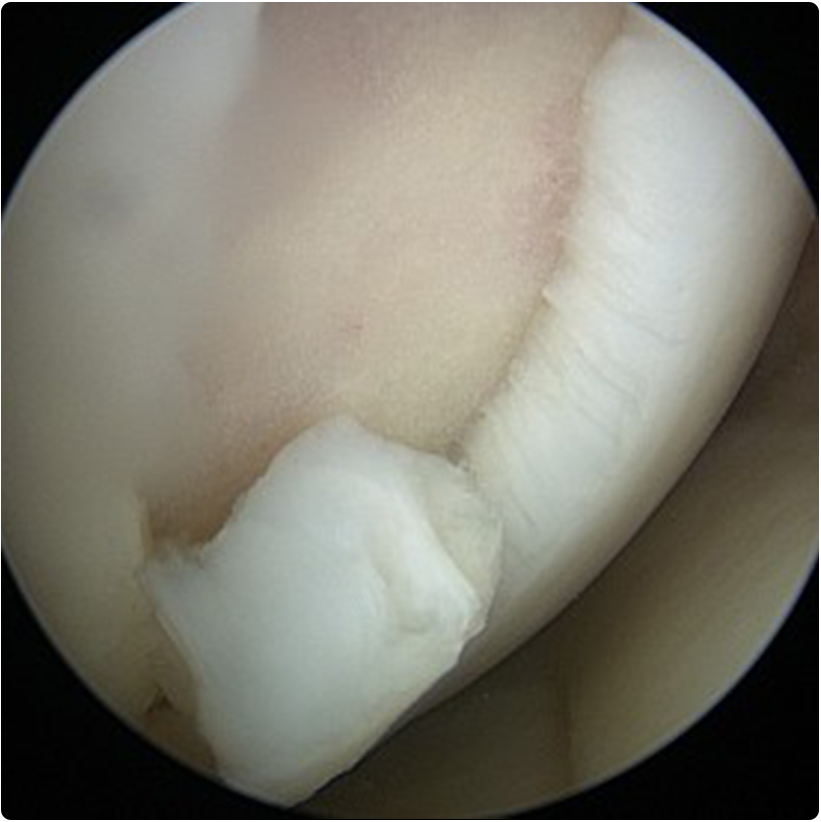

4- Mozaikplasti: yük taşımayan bölgeden alınan silindir şeklinde kıkırdak-kemik dokusu, hasarlı alanda oluşturulan yuvaya yerleştirilir. Böylece orijinal kıkırdakla kaplı, kemik-kemik iyileşmesi olduğu için kıkırdak iyileşmesi beklenmeyen bir iyileşme ortaya çıkar. Özellikle 1-4 cm2arasındaki kıkırdak kayıplarında artroskopik veya açık olarak uygulanabilmektedirler.